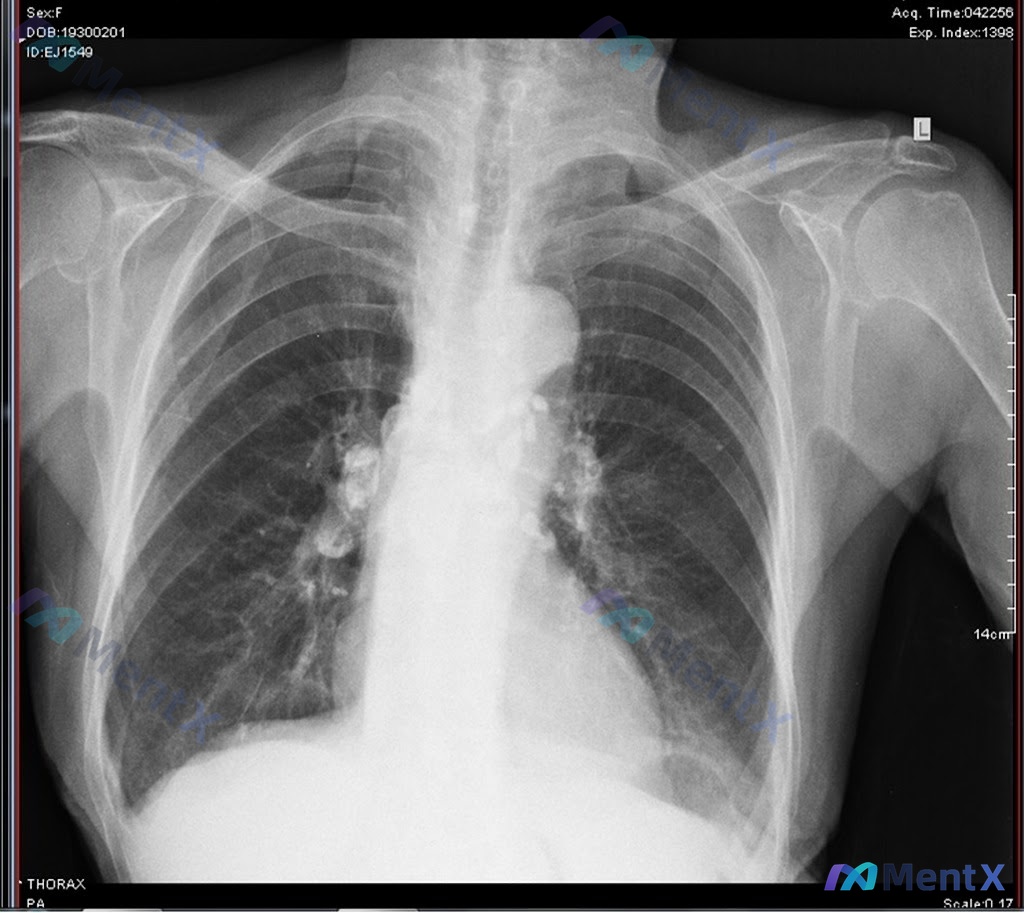

影像检查:胸部正位X光(PA)

先看这次胸片的核心表现:

- 肺门与纵隔:双侧肺门影增大、密度增高,边缘模糊,可见散在高密度钙化灶;主动脉结略突出伴钙化

- 肺实质:双肺纹理增多、增粗、走行紊乱,双肺门周围及中内带可见斑片状、条索状密度增高影,双侧中下肺野有细小结节及索条影;未见明确空洞或大片实变

- 其他:心影大小正常,肋膈角锐利,无胸腔积液/气胸;双侧肩关节退行性改变

这里的核心关键词是「钙化」——双侧肺门的高密度钙化灶,结合双肺的纤维索条影,最符合的是「钙化的分枝杆菌病灶及双侧钙化的肺门淋巴结」,也就是陈旧性肺结核的愈合表现。